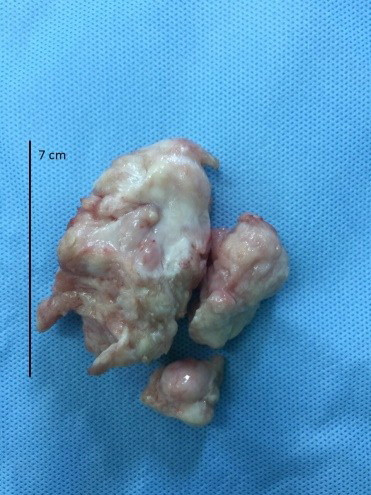

| Khối u rất lớn được lấy ra cho bệnh nhi. (Ảnh : BVCC). |

Trường hợp của bé L.B.P có khối u rất lớn, chiếm gần hết buồng tim thất phải, kích thước 7x4x3.5 cm, gây hẹp nặng, cản trở máu lên phổi.

Sau hơn 4 giờ phẫu thuật, toàn bộ khối u đã được lấy ra khỏi tim. Phần buồng tim còn lại đã được sửa chữa để đảm bảo chức năng tim được bình thường.

Các bác sĩ rất bất ngờ vì bé có thể sống được với khối u lớn như vậy và cũng may mắn là kết quả xét nghiệm mô học cho thấy đây là u sợi lành tính. Như vậy, bé sẽ hoàn toàn bình phục với trái tim khỏe mạnh.